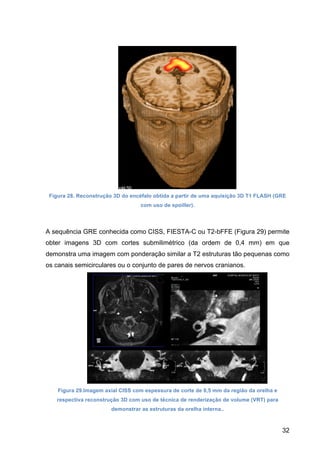

Não só com o objetivo de reformatar as imagens em outros planos, as aquisições 3D

GRE ponderadas em T1 do tecido cerebral (Figura 28) permitem medir o volume de

estruturas cerebrais como os hipocampos e, assim, obter dados quantitativos que

podem ser usados para correlacionar a condições patológicas específicas, como a

doença de Alzheimer.

Figura 28. Reconstrução 3D do encéfalo obtida a partir de uma aquisição 3D T1 FLASH (GRE

com uso de spoiller).

A sequência GRE conhecida como CISS, FIESTA-C ou T2-bFFE (Figura 29) permite

obter imagens 3D com cortes submilimétrico (da ordem de 0,4 mm) em que

demonstra uma imagem com ponderação similar a T2 estruturas tão pequenas como

os canais semicirculares ou o conjunto de pares de nervos cranianos.